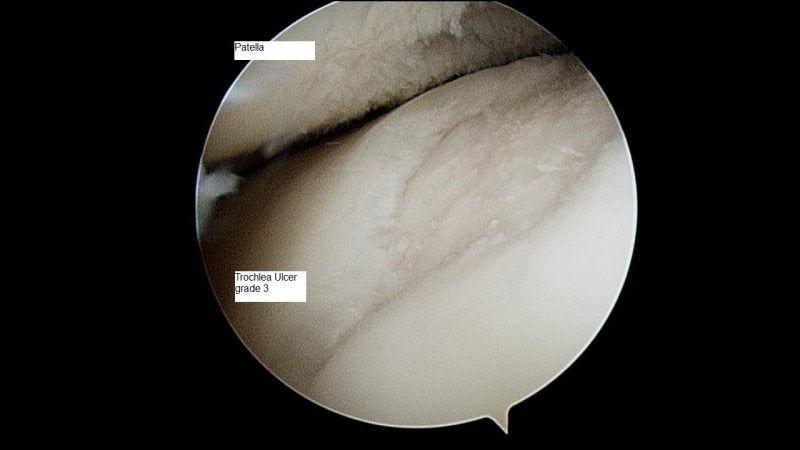

В самом начале протекания первичного гонартроза развиваются патологические изменения в хрящевой ткани на молекулярном уровне. Она становится очень тонкой, склонной к расслаиванию и хаотичному растрескиванию.

По мере прогрессирования болезни хрящ полностью разрушается, приводя к обнажению костей сустава, которые быстро реагируют на нехватку хрящевой ткани и образуют на своей поверхности шипы (остеофиты). Подобное состояние приводит к деформированию и частичному искривлению конечности.

| 2 степень | При переходе болезни во вторую степень человек ощущает первые боли (стартовые). При сгибании ног больной замечает скованность. На снимках рентгена, помимо сужения суставной щели, специалист может выявить костные остеофиты. Двусторонний гонартроз 2 степени приводит к атрофированию мышц бедра |

| 3 степень | Последняя стадия заболевания сопровождается постоянными болями, даже в ночное время. В очаге поражения возникает отечность. Нередка полная блокада сустава: больной не может сгибать или разгибать ногу. При осмотре врач отчетливо видит деформацию коленей |